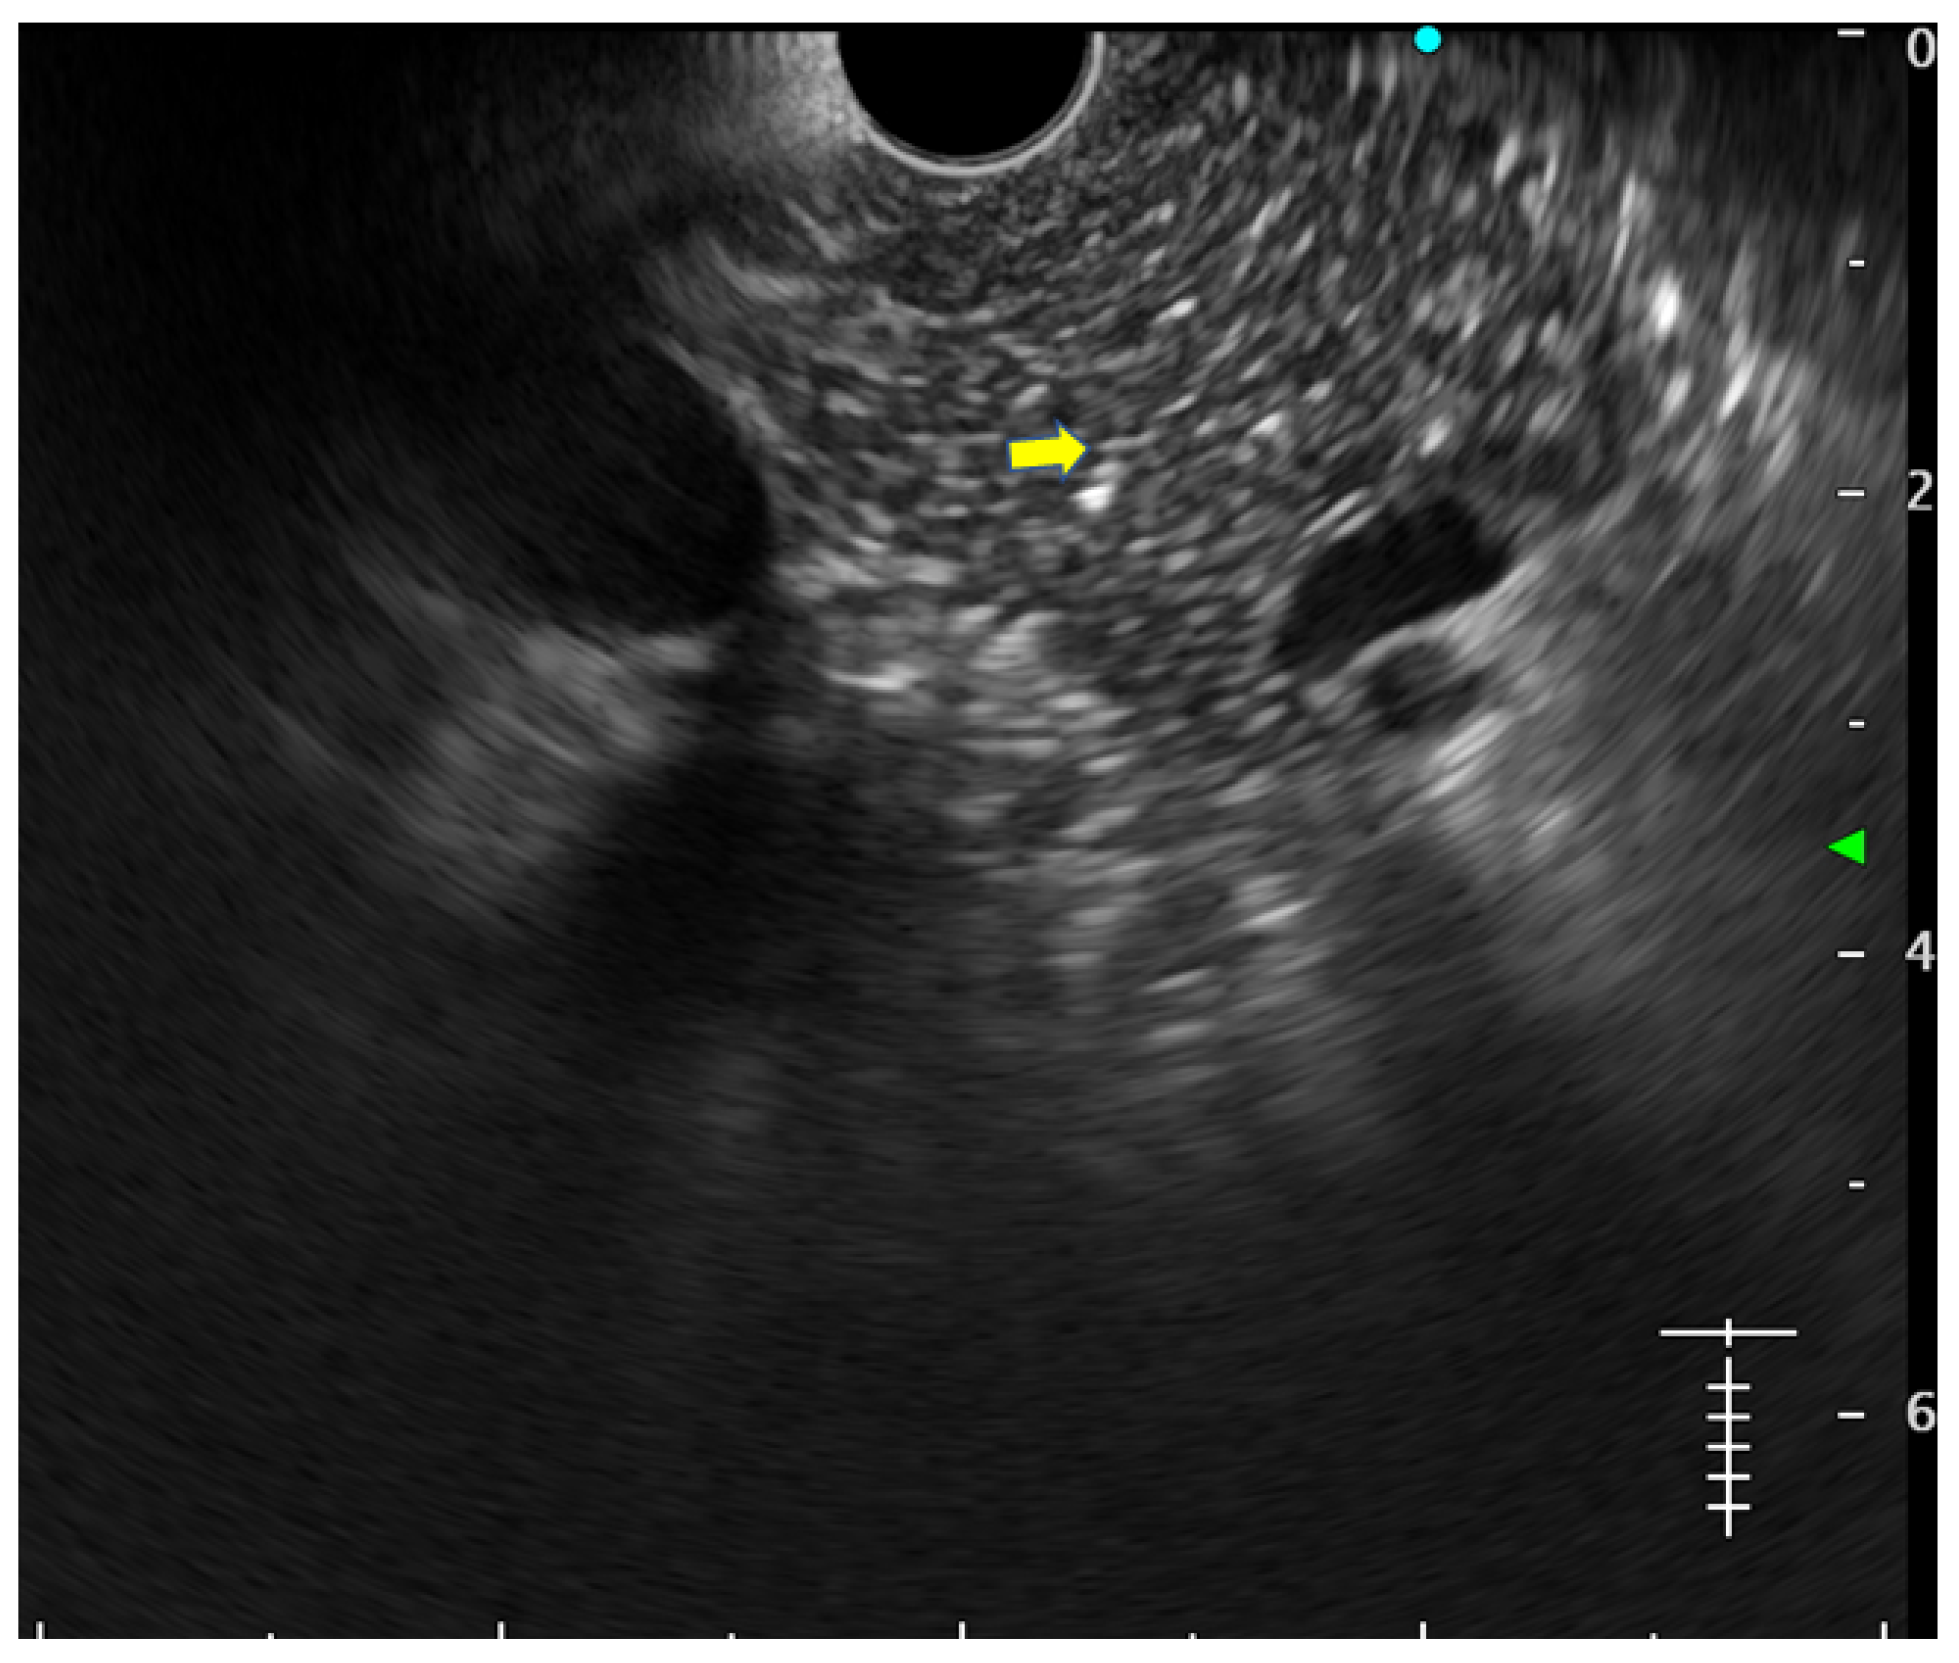

- Hyperechoic foci without shadowing: Echogenic structures of ≥3 mm in length and width without any posterior acoustic shadowing are defined as ‘hyperechoic foci without shadowing’ in the JPS definition. In standard definition, it is included under ‘hyperechoic foci.’ At least three such foci need to be present to be described as abnormal. The presence of acoustic shadowing signifies calcification. Histologically, they correspond to focal fibrosis (Figure 3);